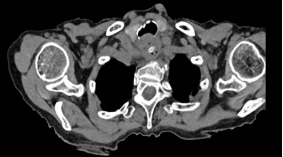

随即,老人转入广元市第一人民医院就诊。CT检查结果显示,一枚长约2厘米的尖锐枣核已刺穿食管壁,且局部已形成脓肿,情况万分危急。食管穿孔本身属于胸外科急症,对于高龄患者而言,穿孔后纵隔感染、脓胸等并发症发生率更高,死亡率可达20%—40%。加之该患者年事已高,还合并多种基础疾病,后续治疗与手术的风险大幅攀升。